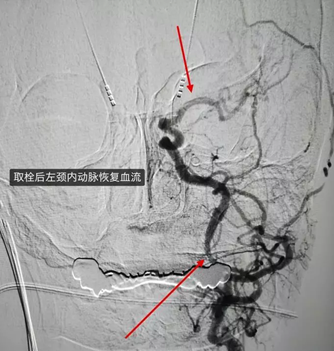

钟婆婆被立即送入DSA室,在局部麻醉下进行的“脑血管造影”检查,检查证实了大家的猜想,钟婆婆从左侧颈内动脉从起始部分就已完全闭塞。

在团队娴熟的技术操作下,仅用一次机械取栓就开通了钟婆婆的左侧颈内动脉,并取出了长达14mm的血栓。从动脉穿刺到血管开通,手术仅用了68分钟。

手术中还发现,钟婆婆左侧颈内动脉起始部狭窄非常严重,很可能是这次中风的主因,为避免老人短期内动脉会再次闭塞,团队还对狭窄处进行了球囊扩张,进一步改善了血流。